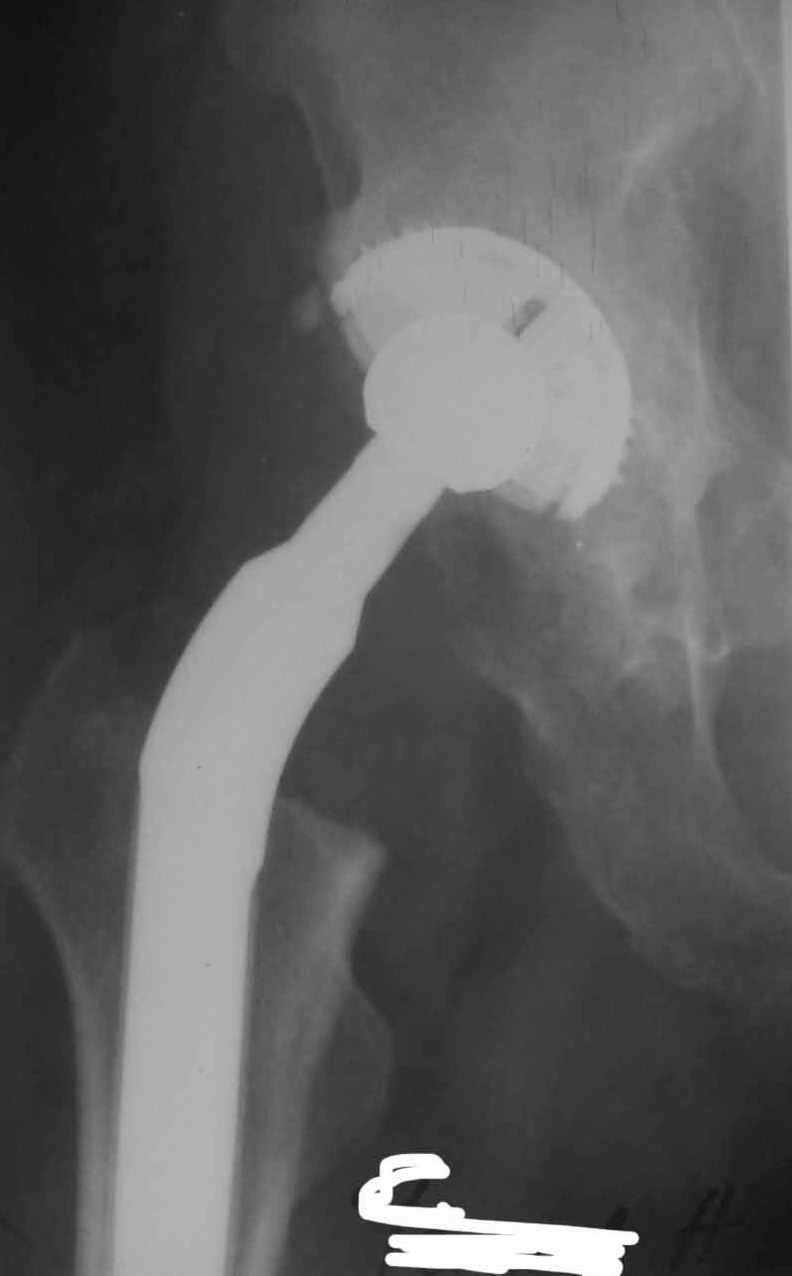

Во вложении - рентгенограммы после вывиха и после вправления.

Консультировать вывихи по рентгенограммам, не зная хода операции, дело не очень благодарное. Я думаю, что с датой операции Вы ошиблись и это был 2004 год? Тем не менее. Настораживают два фактора. Первое - не видно большого вертела. Если с мышцами обошлись грубо и их отсекли, то это очень грустно и нужна "связанная" пара, т.н. "constrain cup". Смущает хорошо прослеживаемый малый вертел и небольшая ретроверсия чашки. Возможно это (избыточная ретроверсия ножки и чашки) могло послужить причиной вывиха. Обычно гипсовая повязка после операции не накладывается, значит, были глубокие сомнения у оперировавшего хирурга. В этом случае - ревизия с перестановкой как минимум - ножки, а как максимум - обоих компонентов.

Идея очень простая, в случае, если удасться прожить без вывиха 2.5-3 месяца, вероятность его возникновения в будущем значительно уменьшится. Оптимальный вариант - повторная иммобилизация на срок 6 недель с нагрузкой на ногу (как бы я ни не любил гипс, но этот путь проверенный и может дать результат). Если это невозможно, то исключительно осторожная реабилитация под строгим контролем без резких движений (спать в положении на спине с отведением и подушкой под коленкой и т.д.). Ходьба сама по себе не опасна, опасен переход от положения "лежа" в положение "полусидя" и "стоя" и наоборот.

Если все же вывих(и) повторятся, то другого выхода, кроме операции нет. Но к ней нужна супер серьезная материальная подготовка о которой я говорил раньше.